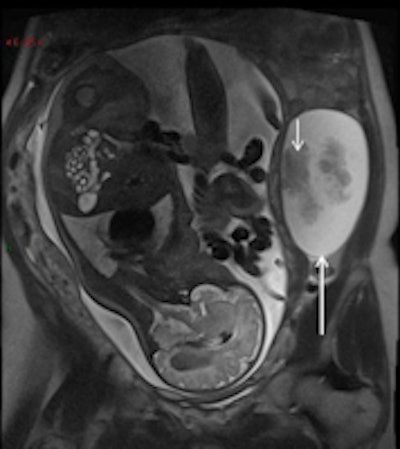

Serous ovarian cystoadenocarcinoma in a 34-year-old woman at 32 weeks gestation presented with acute abdominal pain. Coronal (left) and sagittal (right) T2-weighted MR images show a complex mass, with fluid and solid components (short arrows) on the left ovary.The modality is particularly helpful when the gravid uterus limits ultrasound. However, MRI poses theoretical risks to the fetus, and care must be taken to minimize these with the avoidance of contrast agents.